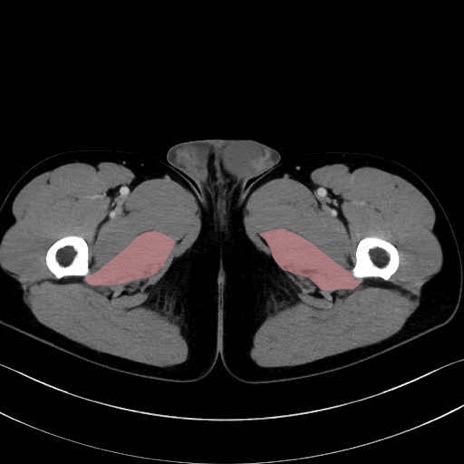

大内転筋(Adductor magnus)、小内転筋(Adductor minimus) のCT画像の解剖

大内転筋・小内転筋 (Adductor magnus / Adductor minimus)